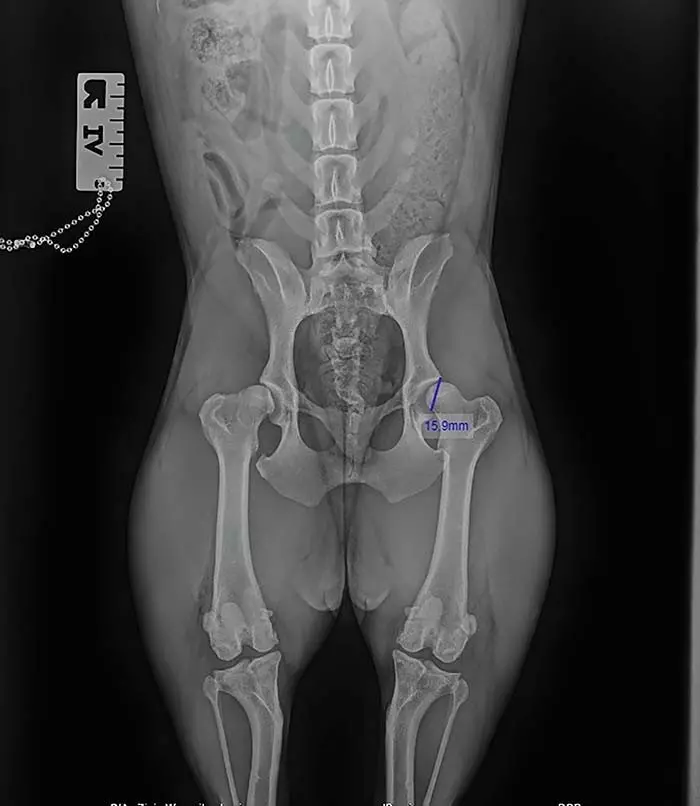

Kolejnym zaburzeniem, który dotyka stawy psich seniorów, jest dysplazja stawu biodrowego/stawu łokciowego (zdj. 2). Jej etiologia jest wieloczynnikowa, gdzie sama dysplazja polega na nieprawidłowym ukształtowaniu się panewki stawowej wskutek deformacji wrodzonej, nieprawidłowego żywienia lub zbyt intensywnego ruchu w wieku szczenięcym. Choroba może przyjmować postać jednostronną lub obustronną, a diagnostyka może stwierdzić pojawienie się nieprawidłowości w budowie stawu już w okresie młodzieńczym.

Zdj. 2. Przykładowa dysplazja stawu biodrowego u buldożka francuskiego